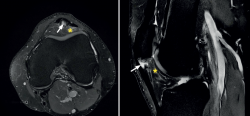

The most common MRI finding is increased signal intensity in the lower pole of the patella, with local widening of the affected zone of the tendon (Figure 7)(14,25). The most evident advantage of MRI with respect to ultrasound is its capacity to visualise associated lesions in the joint and cartilage, as well as the presence of bone edema and involvement of Hoffa's fat pad (Figure 7). As clear disadvantages, mention must be made of the high cost of the technique and the impossibility of performing exploration in motion or at different angles of flexion of the knee.

Figure 7. Magnetic resonance imaging view showing alteration of the proximal patellar tendon with thickening and edema (white arrow), in a segment measuring 1.5 cm in length. Marked edema of adjacent Hoffa's fat pad (asterisk).